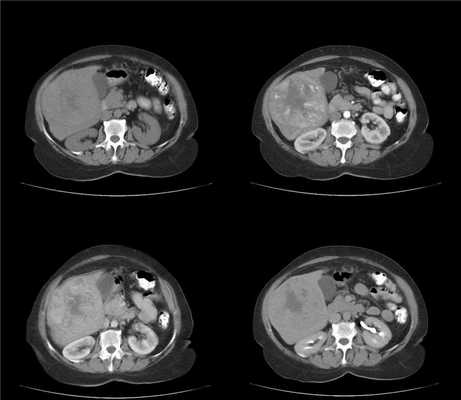

На фоне нерезко выраженых цирротических изменений в виде гетерогенности структуры и неровности контуров печени визуализуется крупное (более 2 см) образование, изоденсное в нативную фазу. В артериальную фазу оно демонстрирует гетерогенное накопление контраста (выше чем паренхима печени). Структура мозаичная, в центре образования участок пониженной плотности - вероятно, центральный некроз. Вокруг образования гиперденсный ободок, выраженый в портовенозную фазу. В отсроченной фазу образование гиподенсно по отношению к окружающей паренхиме печени.